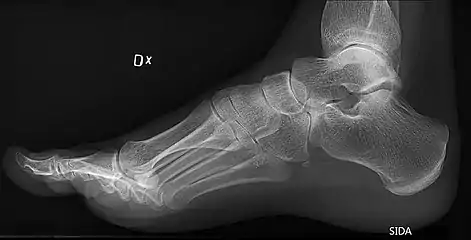

On weightbearing projectional radiography, pes cavus can be diagnosed and graded by several features, the most important being medial peritalar subluxation, increased calcaneal pitch (variable) and abnormal talar-1st metatarsal angle (Meary's angle).[16] Medial peritalar subluxation can be demonstrated by a medially rotated talonavicular coverage angle.[16]

Foot with pes cavus (and os peroneum).